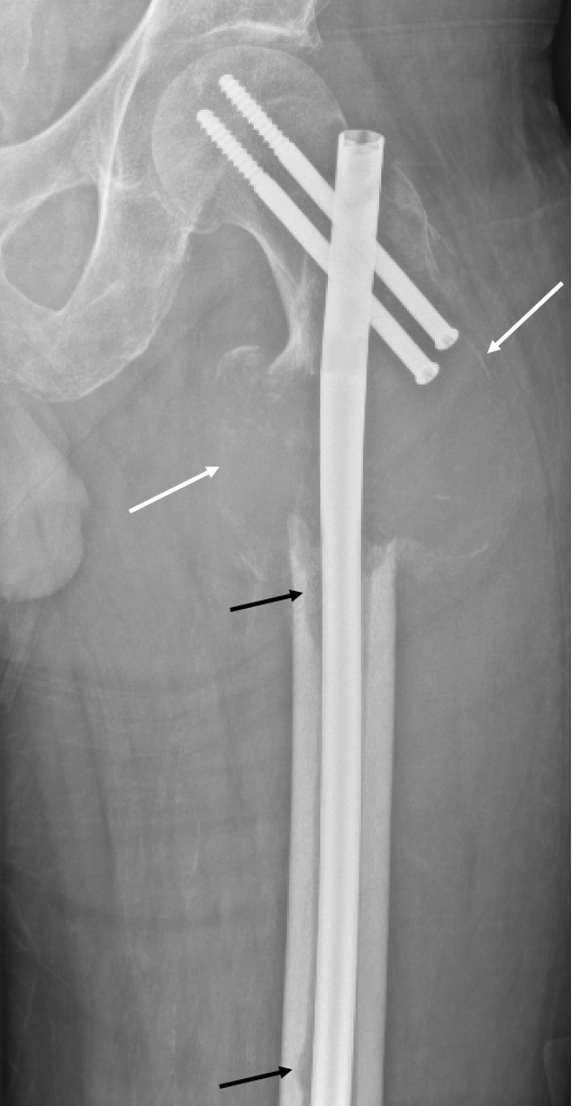

Diagnostic testing. The patient’s initial radiographs from December 2023 demonstrated a lucent lesion (Figure 1) in the proximal femur with cortical thinning, later progressing to a subtrochanteric fracture (Figure 2) and cortical destruction with expansion (Figure 3)1,2, corresponding with biopsy proven fibrous dysplasia with secondary cystic changes.

Figure 3. Plain radiograph of left proximal femur. The lesion has enlarged with increased periosteal bone formation and cortical destruction (white arrows). There are new lucent endosteal foci (black arrows) in the medial mid and distal femoral diaphyseal cortices. Postsurgical changes of intramedullary nailing with interlocking screw fixation of pathologic fracture of the subtrochanteric left proximal femur.